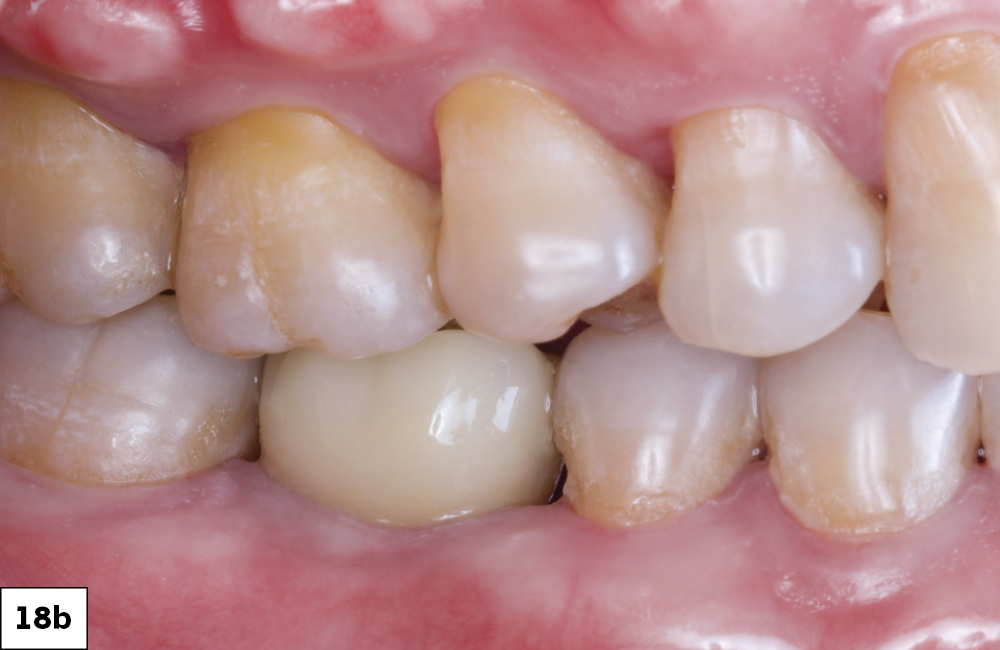

Figures 18a, 18b: The final restoration seated perfectly without the need for any adjustment. The custom healing abutment created an emergence profile that allowed the final restoration to blend seamlessly with the adjacent teeth and appear to emerge from the tissue like a natural tooth. The result blends well with the adjacent dentition, restoring both function and esthetics.